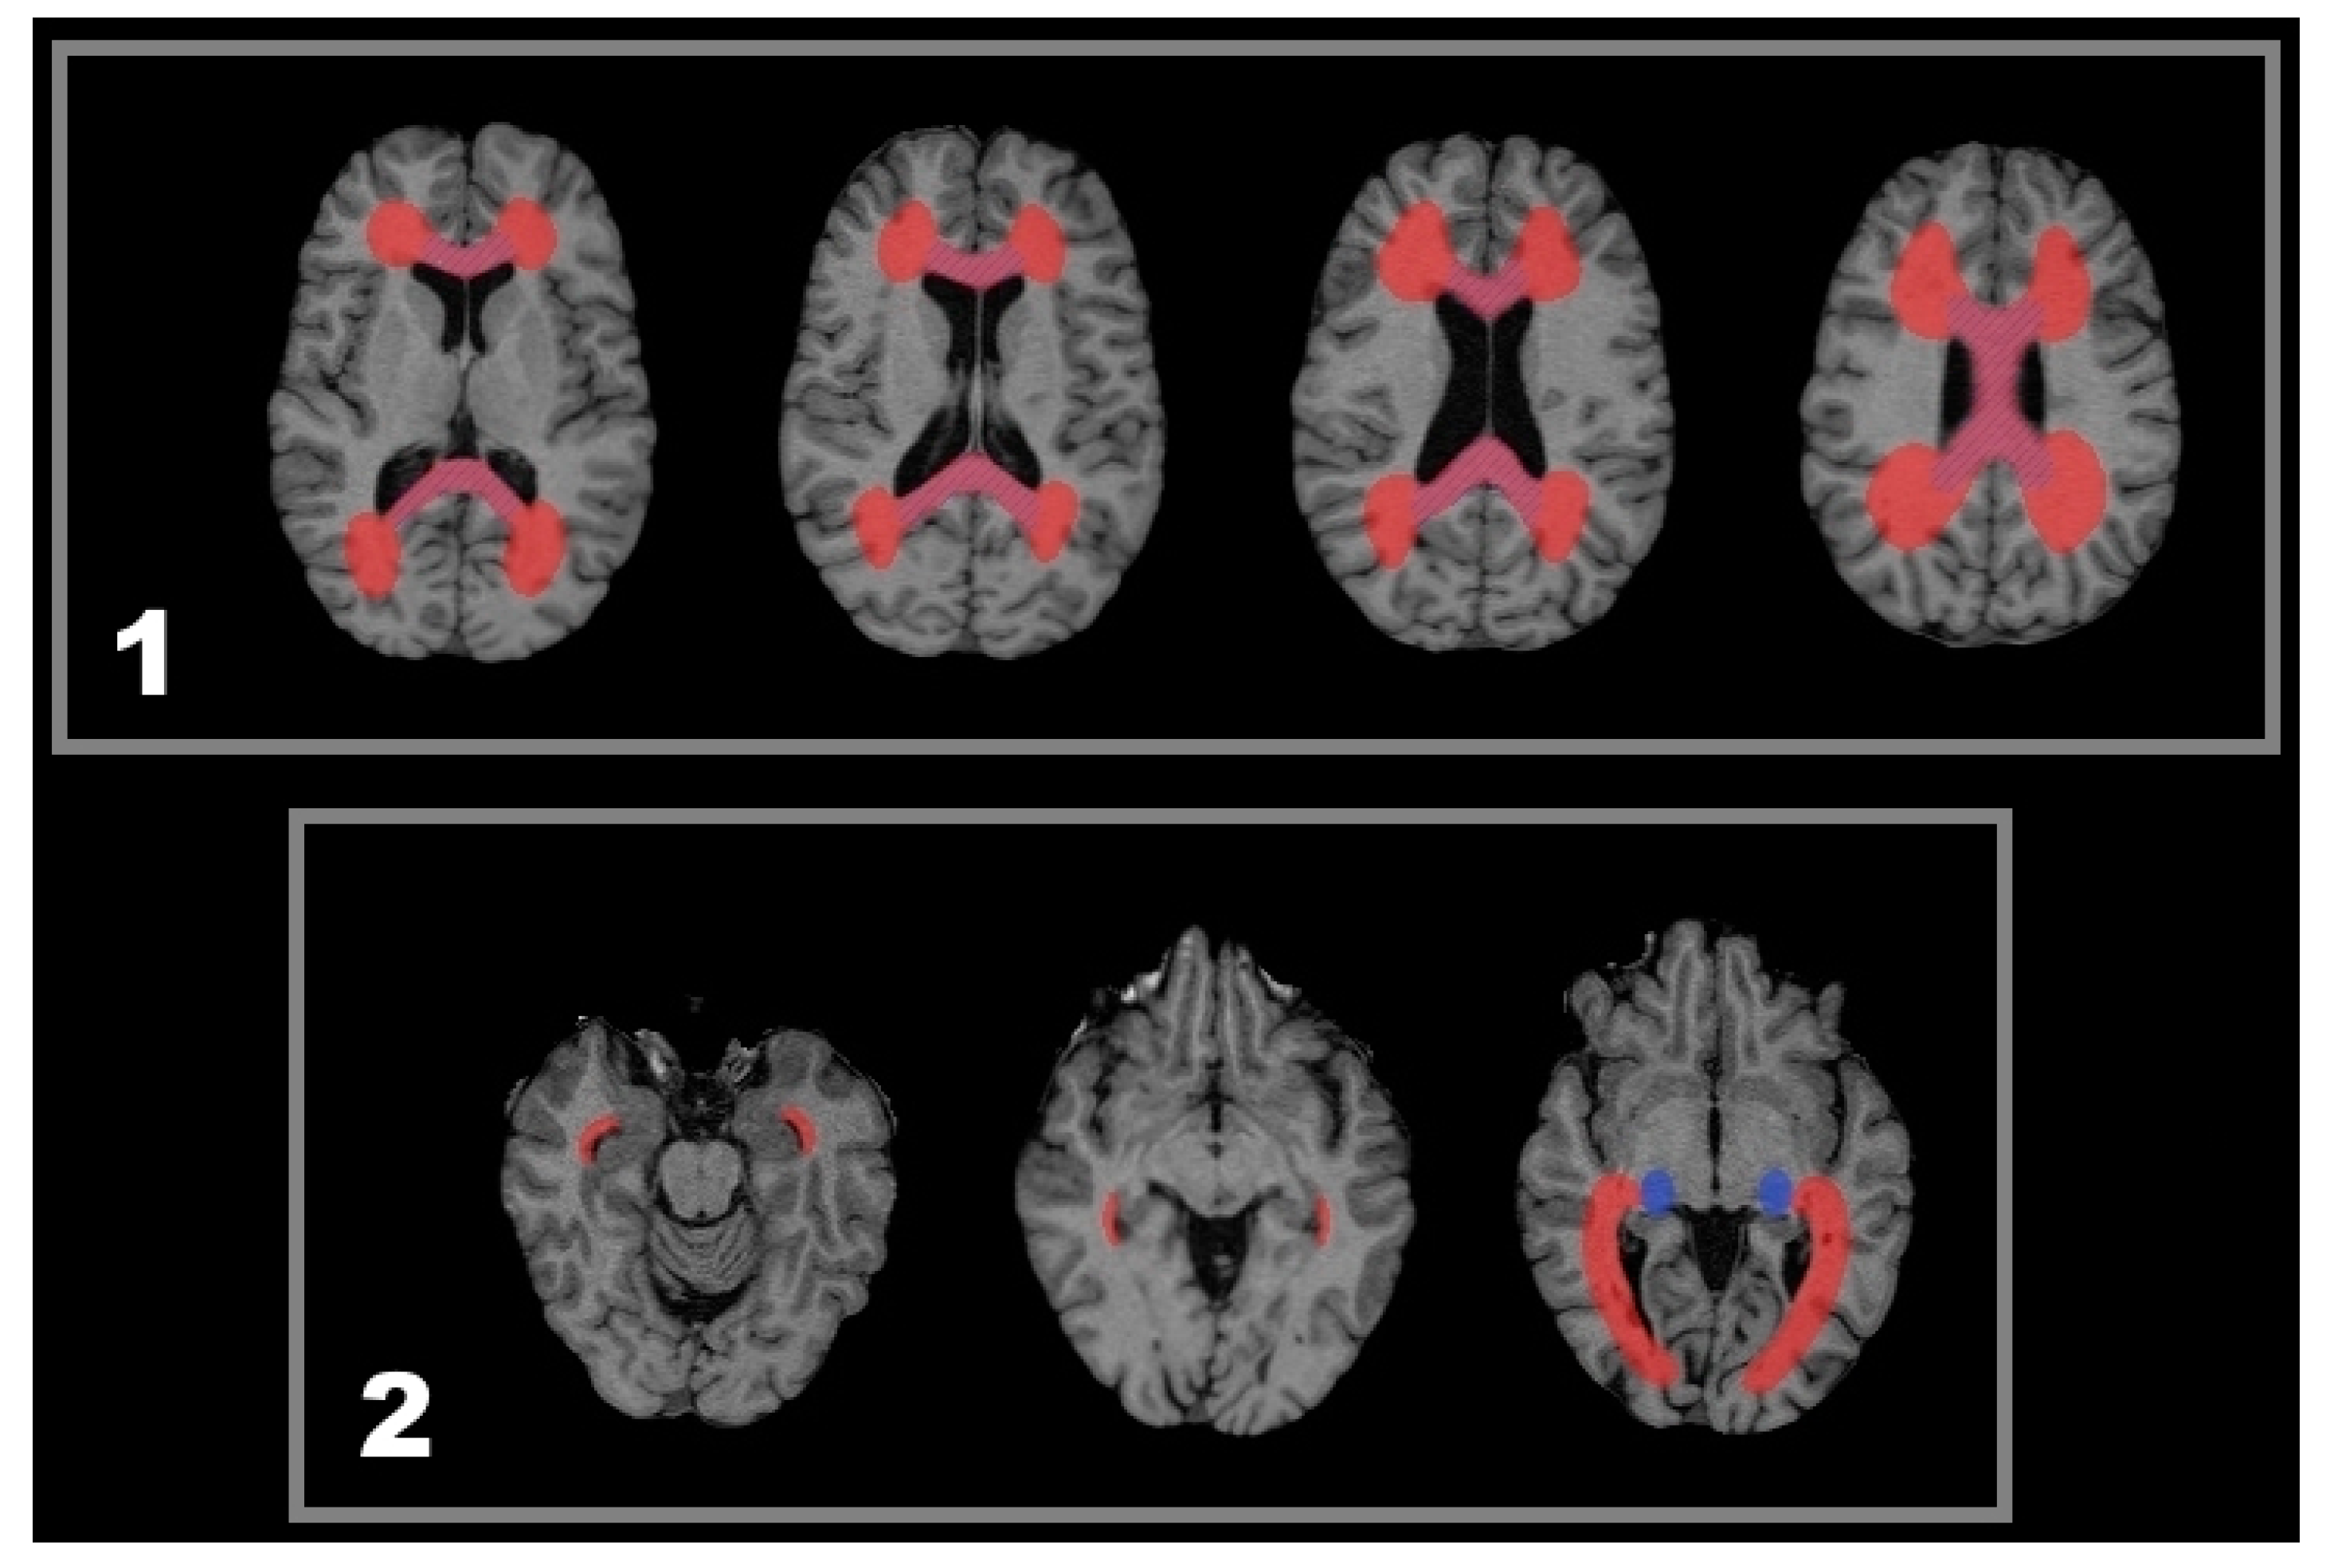

2.2. Lesion-Related Atrophy of the Corpus Callosum and the Lateral Geniculate Nucleus (LGN)

4.2. Segmentation and Voxel-Guided Morphometry (VGM) Processing

4.5. Statistical Analysis—Lesion Related Local Volume Decrease